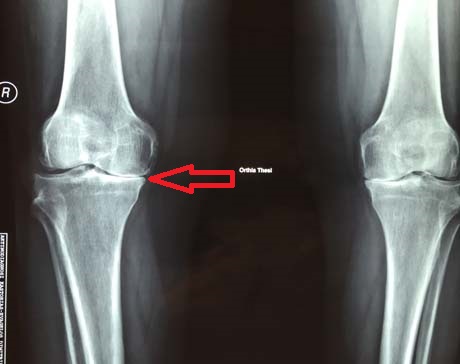

Female 73 years old and weight 122 kg suffering from severe osteoarthritis of the knee bilaterally. The large deformation of the legs combined with the intense knee pain create a big problem in the movement of women.

Pre-op X-ray, severe osteoartrhitis of the knees bilaterally (final stage – bone to bone contact)

Varus deformity of the right knee, which reaches 17.9 degrees without weight bearing the right lower limb